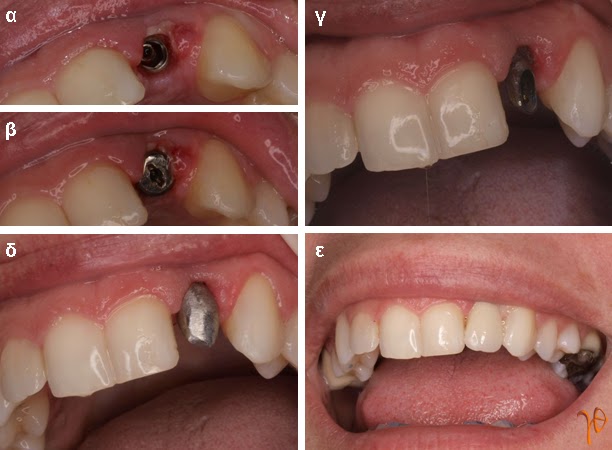

Περίπτωση 1: Αντικατάσταση οδοντικού εμφυτεύματος στη θέση #11

Εικόνα 1.1: (α) τρισδιάστατη απεικόνιση τοποθετημένου εμφυτεύματος #11 με φτωχό αισθητικό αποτέλεσμα και σημεία φλεγμονής με οστεολυσία (βέλη), (β) διεγχειρητική εικόνα εμφυτεύματος (βέλη), (γ) και (δ) αφαίρεση εμφυτεύματος (βέλη)

Εικόνα 1.2: (α) τοποθέτηση νέου εμφυτεύματος στη θέση #11, (β) τοποθέτηση οστικού μοσχεύματος και μεμβράνης με pins (γ) οπισθοφατνιακή ακτινογραφία μετά από τέσσερεις μήνες, (δ) και (ε) μόνιμη προσθετική αποκατάσταση #11.